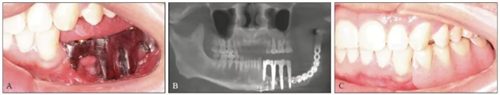

患者2014年6月5日因左下頜腫脹伴觸痛到青島大學(xué)附屬醫(yī)院口腔頜面外科就診,診斷為左側(cè)下頜骨成釉細(xì)胞瘤。全景片示左側(cè)下頜第二前磨牙遠(yuǎn)中至乙狀切跡處可見多房低密度影,左下頜第一磨牙遠(yuǎn)中根可見明顯吸收(圖1)。

2014年6月9日于本院行下頜骨左側(cè)成釉細(xì)胞瘤切除術(shù)+下頜骨節(jié)段性切除術(shù)+重建板重建術(shù)+血管化腓骨肌皮瓣轉(zhuǎn)移修復(fù)術(shù)+鈦板內(nèi)固定術(shù)+血管吻合術(shù)+牽引釘植入術(shù)+拔牙術(shù)(圖2)。

2016年3月22日復(fù)查,全景片示34~37牙缺失,左下頜單層腓骨移植,腓骨與下頜骨對接處骨愈合良好,鈦板鈦釘在位(圖3)。